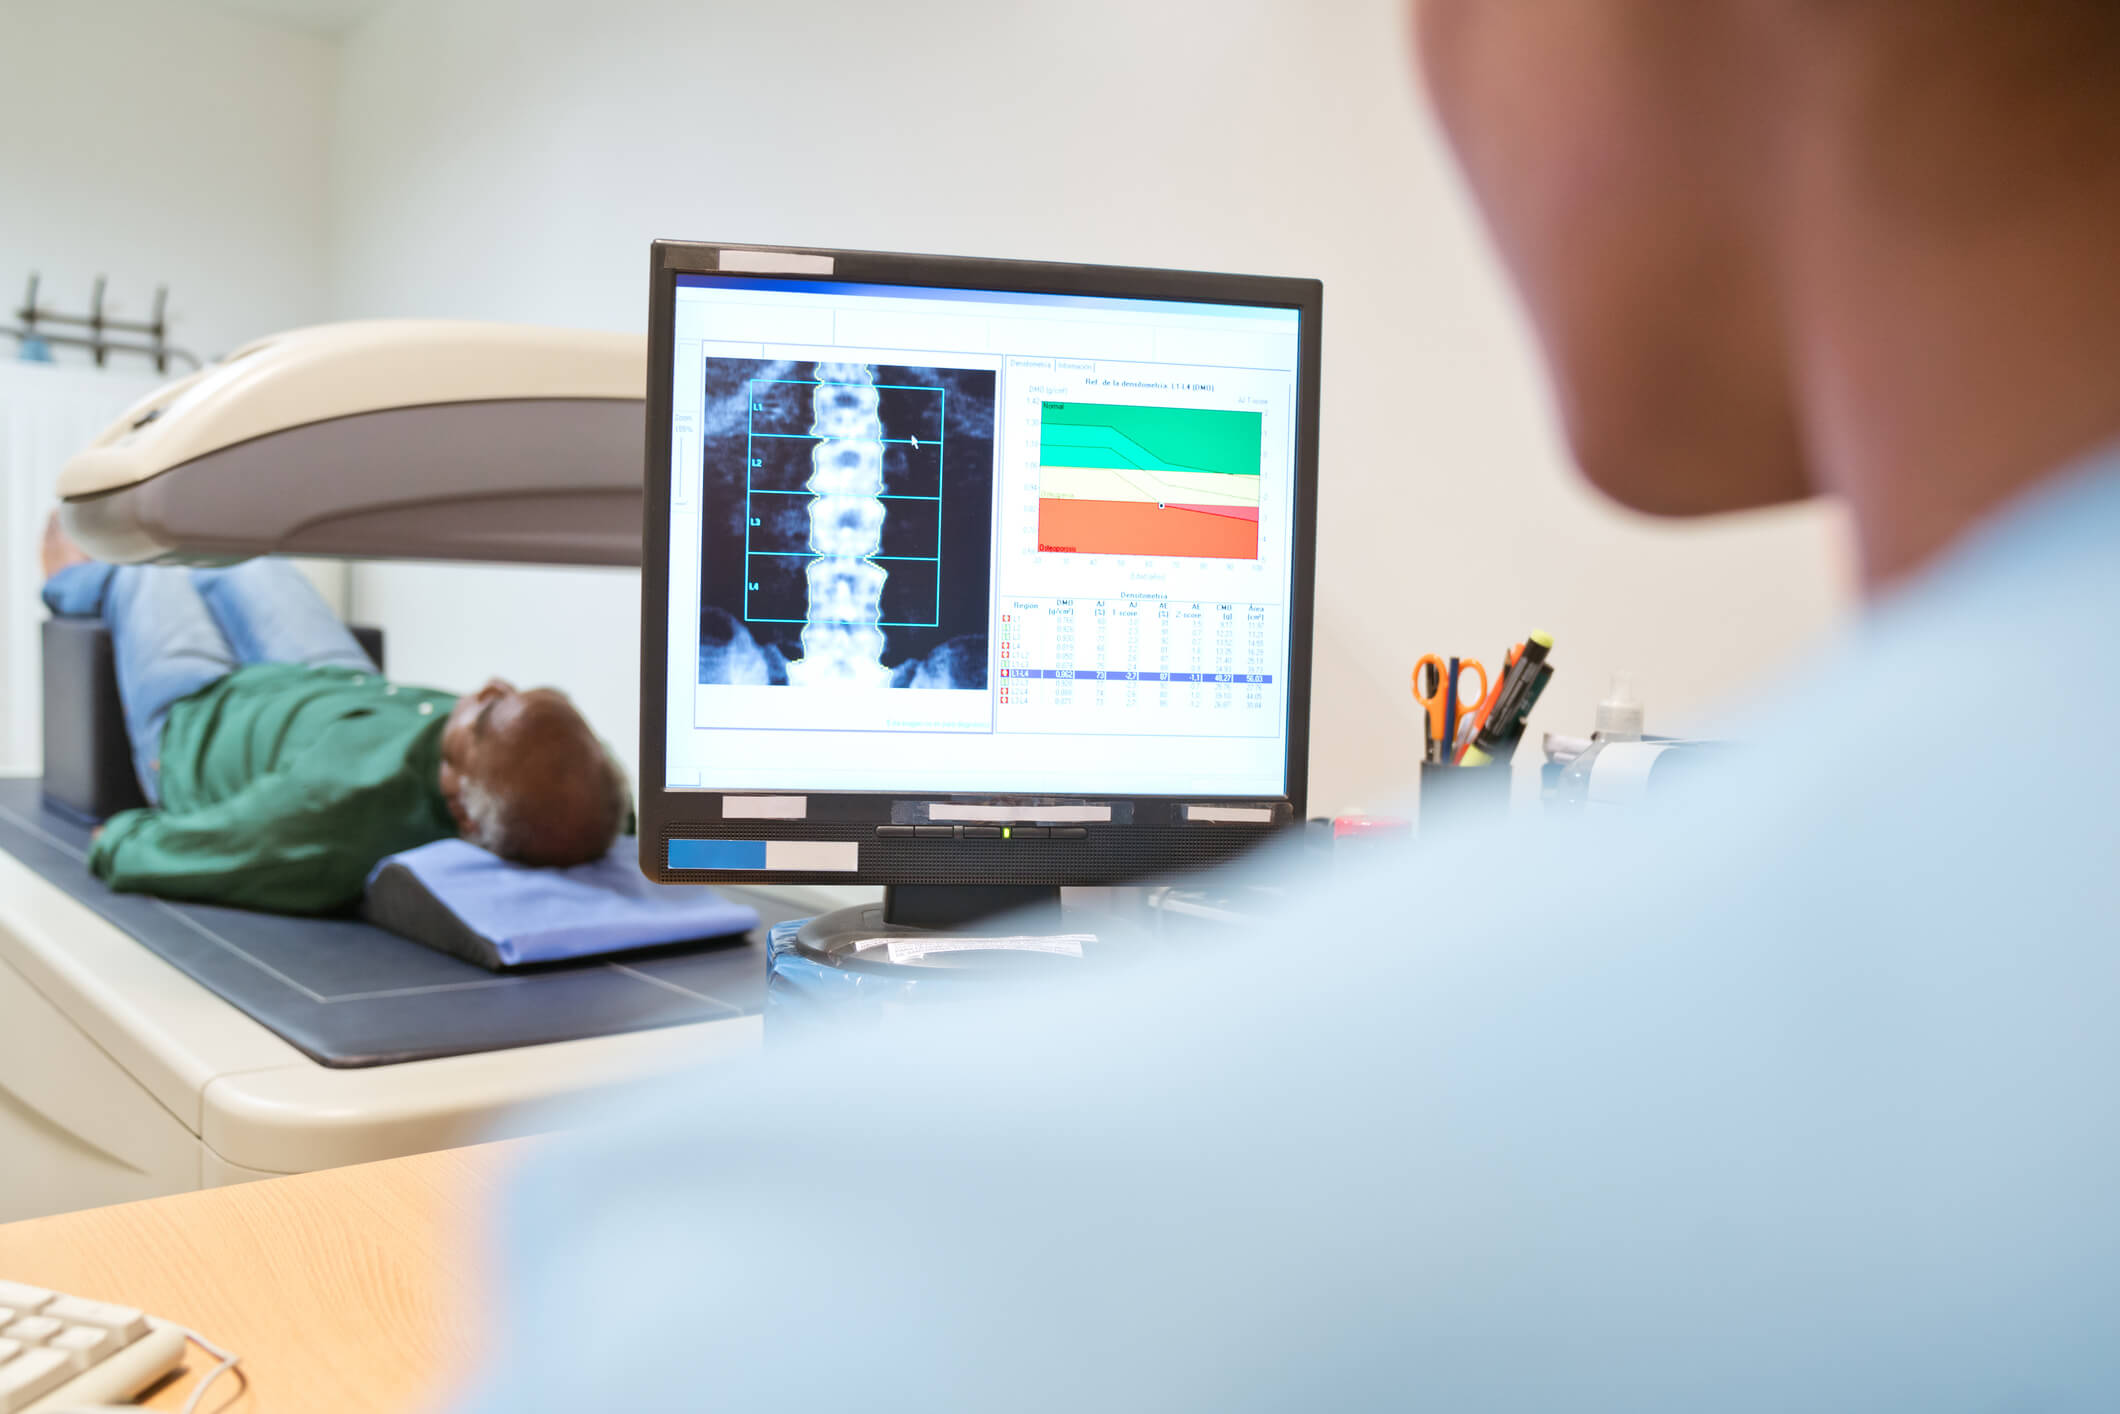

После рентгена, КТ или МРТ пациента могут направить на денситометрию. Мы уже упоминали ее, когда рассказывали об остеопорозе. Это рентгенологическое исследование с последующей компьютерной обработкой результатов, которое позволяет оценить минеральную плотность костной ткани. Именно с помощью денситометрии диагностируют ОП 4, 5.

Поводом направить пациента с переломом на это исследование могут стать обстоятельства, при которых получена травма. Был небольшой удар, падение с высоты своего роста или меньшей, кашель или чихание? Сила воздействия несопоставима с характером повреждения — это может быть признаком остеопороза 1.